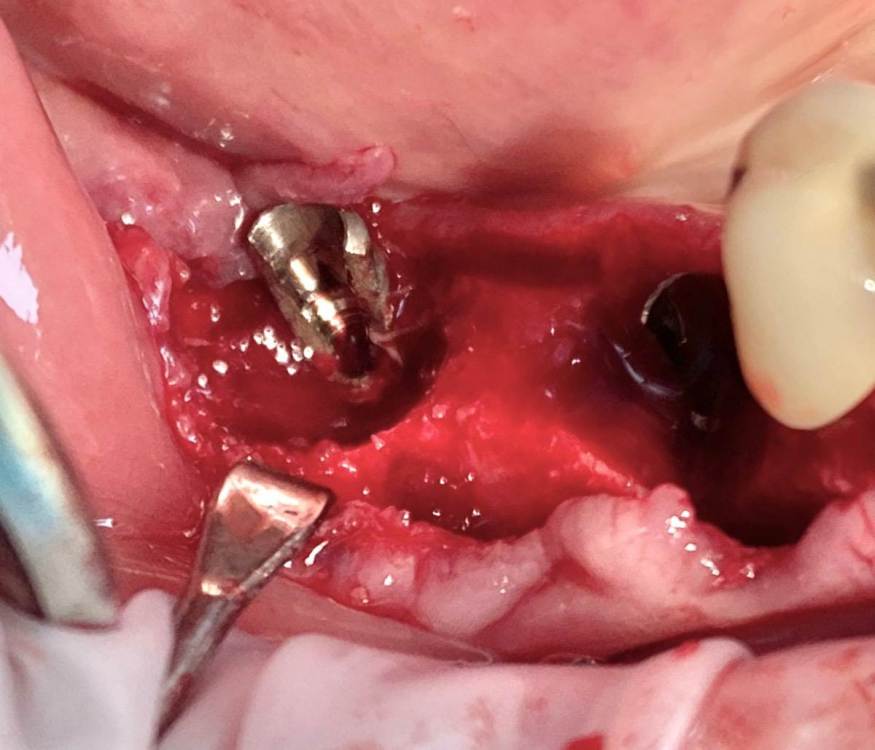

колесников Опубликовано 6 июля, 2022 Поделиться Опубликовано 6 июля, 2022 Здравствуйте коллеги! Впервые вижу перелом Астры. Впервые получил перелом «своей»Астры. Вероятно ещё никто не видел перелом Астры профайл. Диаметры 4.5 и 5.0. Самое неприятное что это произошло за 1,5 года. Ошибка протезирования. Перегруз. Резорбция. Фрактура. Из интересного. Одновременно с имплантацией была произведена контурная пластика поднадкостнично,графт шурос. Это работает. Ставим галочки и двигаемся дальше. 2 1 1 Ссылка на комментарий

колесников Опубликовано 6 июля, 2022 Автор Поделиться Опубликовано 6 июля, 2022 5 часов назад, Aquarius сказал: Спасибо за столь познавательный кейс!!! Я где- то читал, что вроде как перегруза на полностью интегрированных имплантах быть не может. Вроде как первично надо высвободить какую-то площадь импланта от кости ( воспаление, резорбция) чтобы он треснул. А не наоборот. Автор сего высказывания ссылался на то, что в связке имплант-коронка есть куда более слабые места , чем стенка интегрированного импланта. Например, фиксирующий винт. Для конического соединения это утверждение не применимо. Очень часто получаем холодную сварку имплант-абатмент,винт совершенно не работает. Протокол отработан как автомат Калашникова,платформа относительно Зенита и вершины гребня,высота уступа,наличие и ширина прикреплённой слизистой. Далее процесс запускается вспять и через два года наблюдаем прирост кости на скосе гребня. Радиальная Резорбция в виде кратера это всегда перегруз. Импланты не болят. Вокруг них нет посредника-связки,нет проприорецепции. Между тем диссонанс окклюзии со временем нарастает,тк зачастую имеются разнородные по плотности материалы в полости рта. Отчасти пациент тут виноват,не продолжил лечение,пропал на год. Но основная вина ортопеда. Причина личная. Коронка на 45 осталась от старого моста,44 вовсе пародонтитный. Желая их «спасти» вывел из прикуса,основная нагрузка справа упала на импланты. Третий сектор провисший мост 34.35-38 с подвижными 34,35 ,оставлен не тронутым. Хорошая хирургия пошла в утиль по причине малодушия. В итоге когда я стал все это разматывать и рисовать перспективы,пациент сам настоял на тотальной работе. Слабину не даём,за всеми следим. 1 Ссылка на комментарий

Irouil Опубликовано 11 июля, 2022 Поделиться Опубликовано 11 июля, 2022 (изменено) По фото невозможно понять что там было заглубленно и что нет, на рентгене картина объективнее Я вижу из возможных косяков пл хирургии только избыточно лингвальное позиционирование платформы у одного из винтов, из-за чего стенка очень тонкая - если там случилась резорбция, то иллюзию недозаглубения на фото она вполне может создать К тому же, ТС раньше рассказывал что часто идёт на тунельную твердотканную аугментацию при имплантации в таких случаях, если тут тоже - то для меня неточное позиционирование объясняется именно тунельным подходом и ограниченным обзором по такому поводу. Это, в сущности, единственное, что останавливает меня самого попробовать подобную аугментацию как альтернативу минисосиджу. Но надо услышать ТС, это только мои догадки Изменено 11 июля, 2022 пользователем Irouil Ссылка на комментарий

TIGER Опубликовано 11 июля, 2022 Поделиться Опубликовано 11 июля, 2022 @Irouil ну тут много ума не надо и трёхмёрной информации,чтобы понять исходя из этого фото,что там изначальный недозаглуб был (платформа торчит на уровне десневого края),плюс фактор протетики возможно сыграл....? Ссылка на комментарий

Astronaft Опубликовано 12 июля, 2022 Поделиться Опубликовано 12 июля, 2022 (изменено) 06.07.2022 в 14:28, колесников сказал: Протокол отработан как автомат Калашникова,платформа относительно Зенита и вершины гребня,высота уступа,наличие и ширина прикреплённой слизистой. Далее процесс запускается вспять и через два года наблюдаем прирост кости на скосе гребня. Это хорошай заговор-пожелание. В жизни часто не так. По одной простой причине общее здоровье человека влияет намного сильнее. Пародонтологический статус - если есть карманы хоть 5-6мм где-то во рту риск пери-имплантных явлений возрастает. Микробиота слюны, вязкость, диета, качество гигиены, обший воспалительный фон- это сфера влияния пациента. Качественное местное исполнение это хороший фундамент - только одна из составляющих. Астра Профаил - укороченный, асимметричый конус. 3мм с одной стороны, 2мм с другой. Конфигурация перелома закономерна - сами абатменты раскололи высокую стенку от низкой. Я бы предположил что тещины первичны, резорбция это следствие. Изменено 12 июля, 2022 пользователем Astronaft 2 4 Ссылка на комментарий